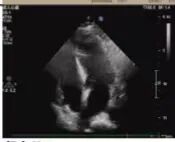

術(shù)前超聲

2025年深秋的一個(gè)清晨,82歲的馬奶奶(化名)因持續(xù)胸悶氣短被家人送至醫(yī)院心內(nèi)科。心臟超聲檢查顯示,她的左心房?jī)?nèi)有一個(gè)直徑近5厘米的腫瘤,隨心跳規(guī)律擺動(dòng),如同一個(gè)隨時(shí)可能破裂的“不定時(shí)炸彈”。更危急的是,冠脈造影進(jìn)一步揭示其冠狀動(dòng)脈多支血管?chē)?yán)重狹窄,左前降支狹窄達(dá)95%,回旋支中段完全閉塞,右冠狀動(dòng)脈彌漫性病變—兩種致命性心臟疾病的疊加,讓這位高齡患者的生命岌岌可危。